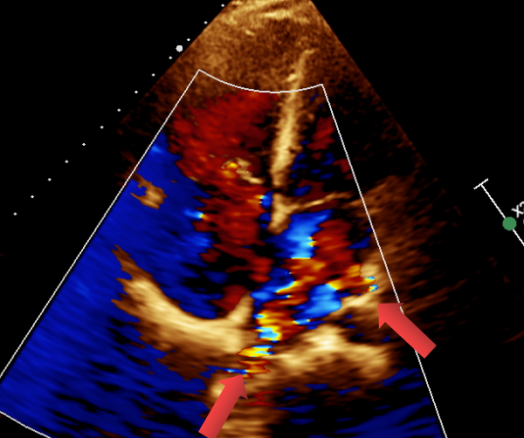

图 1 四腔心切面显示房间隔上可探及宽约 13mm 回声失落,房顶部未见明显

图 2 四腔心切面显示至少两支肺静脉引流入左房

图 4 CDFI 显示房水平可见左向右分流